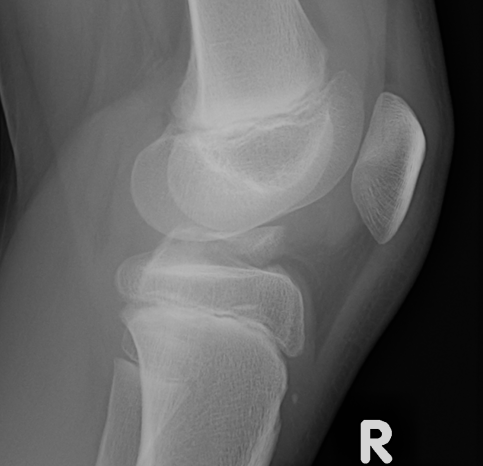

Adolescent boys

Proximal tibia / primary ossification centre

Tibial tuberosity / secondary ossification centre

- eventually merges with primary ossification centre

Type I - Tibial tuberosity ossification only